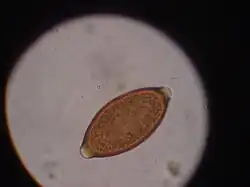

Egg of T. vulpis

Trichuris vulpis is a whipworm that lives in the large intestine of canines in its adult stages. Out of different types of worms, Trichuris vulpis is one of the smaller worms with a size ranging from 30–50 mm in length. As the name suggests, the worm has a whip-like shape with distinct features including a small, narrow anterior head, which is the digestive part of the worm, and a larger posterior tail, which is the reproductive part of the worm. Eggs from T. vulpis are oval shaped with bipolar plugs and contain a thick outer shell. Their sizes range from 72–90 μm in length and 32–40 μm in width.[1] Because of their thick outer shell, T. vulpis eggs are very resistant to environmental extremes such as freezing or hot temperatures, thus allowing for their long viability in the outside world.[2]

The life cycle of Trichuris vulpis begins with the adult whipworms living in the large intestines of dogs. T. vulpis lay many eggs in the large intestine and are released in the feces into the outside environment. When eggs are released into the outside environment, these unembryonated eggs are able to form embryos in the soil in about 2–4 weeks, at which point they become infective when ingested by the new host. An infective larva develops within the egg before it is even ingested by the new host.[3]